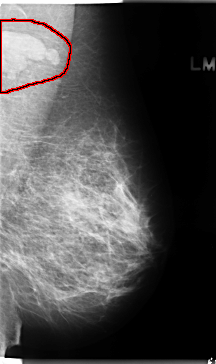

C_0136_1.RIGHT_MLO

LEFT_MLO LINES 4728 PIXELS_PER_LINE 2808 BITS_PER_PIXEL 12 RESOLUTION 50 OVERLAY

FILE: C_0136_1.LEFT_MLO.OVERLAY

TOTAL_ABNORMALITIES 1

ABNORMALITY 1

LESION_TYPE MASS SHAPE LOBULATED MARGINS CIRCUMSCRIBED

ASSESSMENT 5

SUBTLETY 5

PATHOLOGY MALIGNANT

TOTAL_OUTLINES 1

BOUNDARY